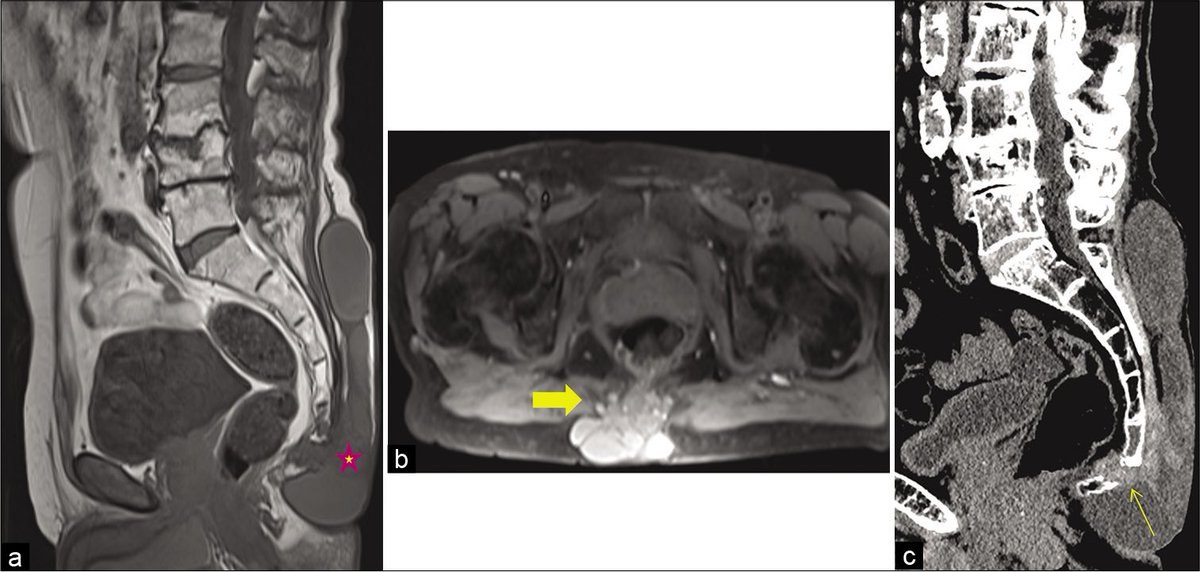

Unraveling a rare cause of spinal stenosis: Coexistent AL and ATTR amyloidosis involving the ligamentum flavum